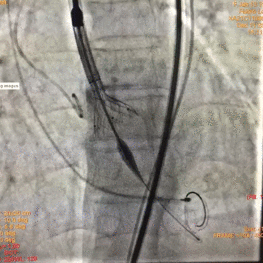

图片

根部造影

球囊预扩

瓣膜释放至2/3造影观察

瓣膜释放后形态欠佳

经球囊后扩后瓣膜形态良好

手术结果

术后造影及超声探查未见瓣周漏,跨瓣压差术前183mmHg,术后几乎无压差,术中及术后未出现相关并发症,手术圆满完成。